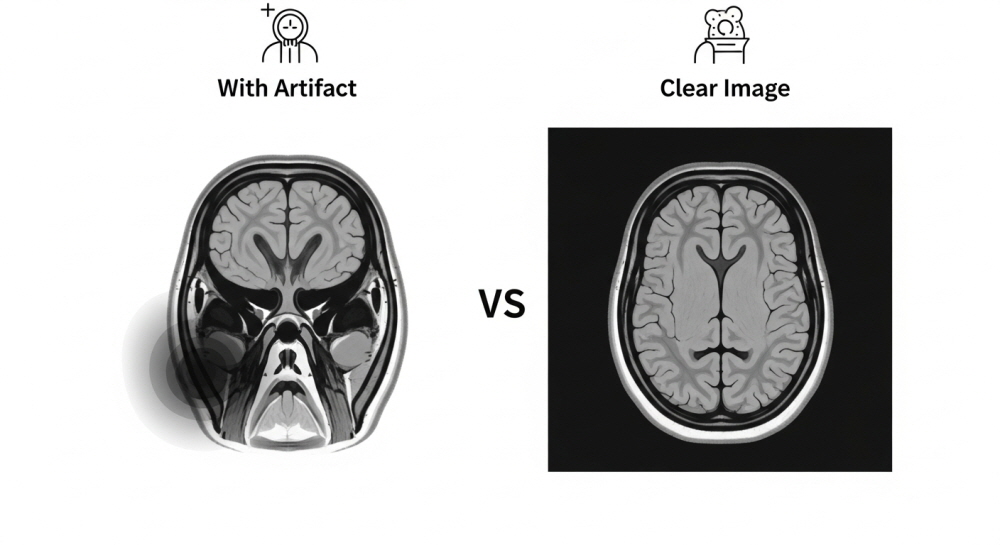

H2. 진짜 문제는 '이것'입니다: MRI 영상 왜곡 (Artifact)

사실 임플란트 환자가 MRI 검사 시 진짜 신경 써야 할 부분은 안전사고보다 '검사의 정확도' 문제입니다. 비자성인 티타늄이라도 금속은 자기장을 미세하게 교란시켜 MRI 영상에 '인공물(Artifact)'이라는 허상이나 왜곡을 만듭니다.

쉽게 말해, 임플란트 주변 부위가 검게 나오거나 번져 보여서 정확한 진단을 방해할 수 있습니다. 특히 뇌나 목, 안면 부위처럼 임플란트와 가까운 곳을 촬영할 때 이 문제가 두드러질 수 있습니다.